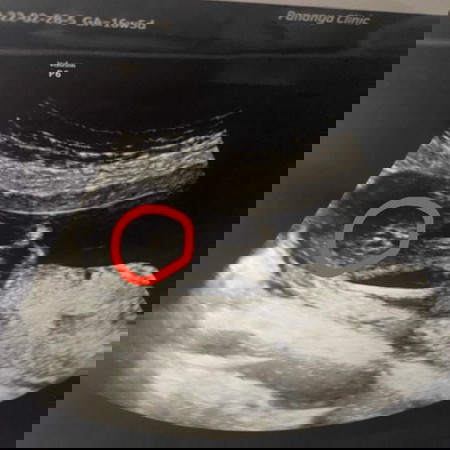

แม่ๆช่วยดูหน่อยค่ะ ญ ช ค่ะ 16วีค5วัน

เหมือนจะญ.นะคะ

เหมือนเห็นกีบน้องค่ะ เพราะถ้าเป็นผช.จะมีจู๋โผล่เลยค่ะ🤣